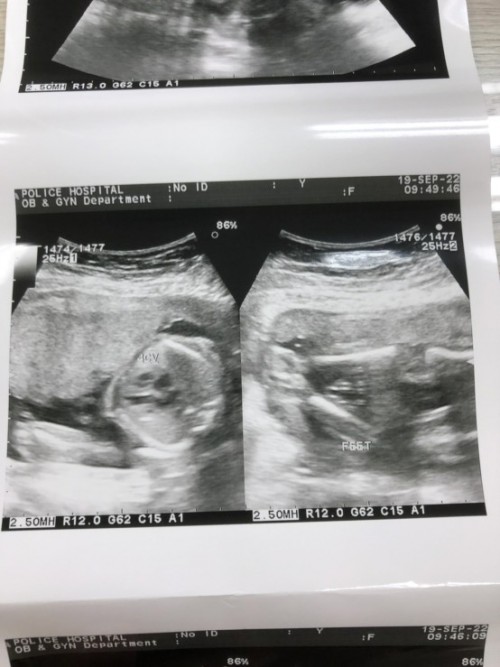

Post reply image

บ้านนี้18มกราคม 66